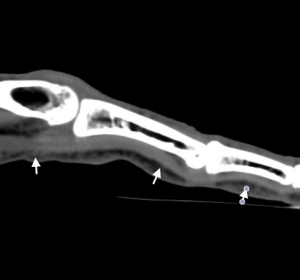

A la face palmaire des doigts, on retrouve les tendons fléchisseurs superficiels et profonds

- A la paume de la main, le tendon fléchisseur superficiel se superpose au tendon fléchisseur profond.

- Au niveau de l'articulation métacarpo-phalangienne, le tendon fléchisseur superficiel enveloppe le tendon profond. Puis, il se bifurque en 2 languettes latérales, qui se réunissent presque immédiatement après, formant ainsi une boutonnière longitudinale à hauteur de la phalange proximale.

Le tendon fléchisseur profond, perfore le tendon superficiel.

- Au niveau de la phalange moyenne, les bandelettes latérales du fléchisseur superficiel viennent s'insérer sur les bords latéraux de l'extrémité distale de P2

- Au niveau de la phalange distale, le tendon fléchisseur profond, vient se terminer en éventail sur l'extrémité distale de P3